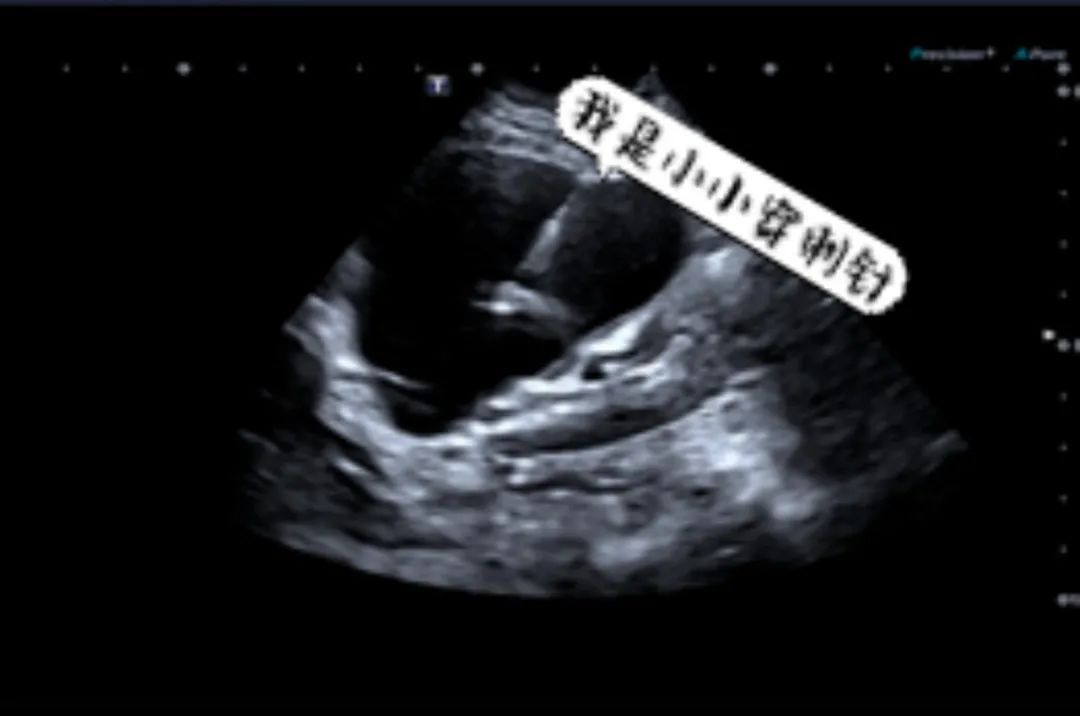

超声引导下囊肿硬化治疗术

在超声实时引导下用一根细细的针“瞄准”囊肿进行穿刺,先抽出囊肿内部的囊液,然后向囊腔内注入硬化剂(如聚桂醇等)以破坏囊肿内壁的细胞,让它不再分泌囊液,从而使囊肿缩小、闭合,逐步吸收并消失。